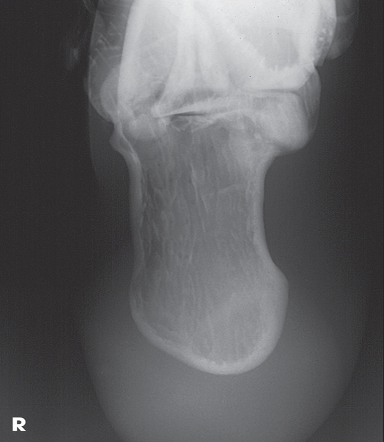

Name this projection.

Lateral calcaneus

What type of projection is it?

Mediolateral

Is the patient on the affected or unaffected side?

Affected

State specifically where the CR enters.

Perpendicular to the calcaneus // 1" distal to the medial malleolus

Which tarsal is in profile?

Calcaneus

Which radiographically significant landmark is open?

Sinus tarsi